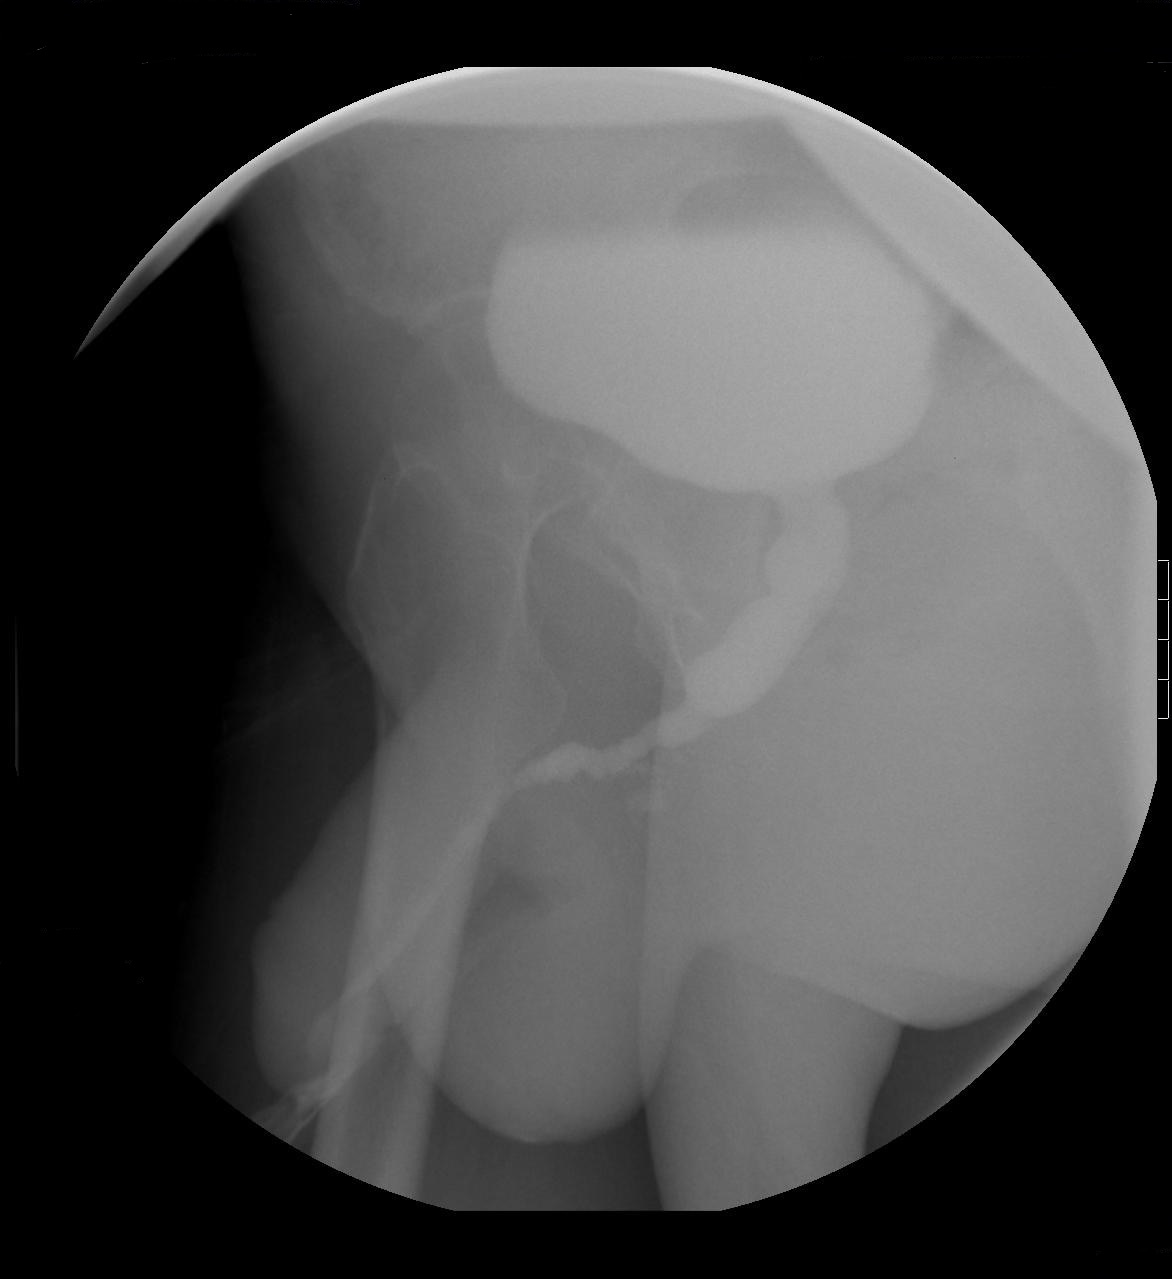

Uretrografía Retrógrada (UGR)